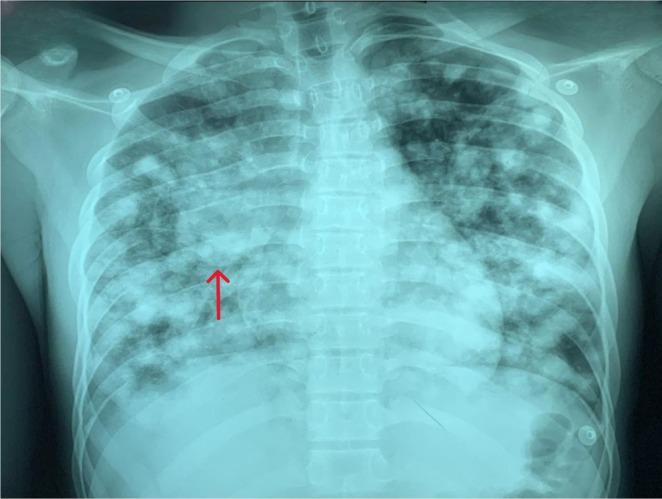

A previously healthy teenager presented with acute respiratory distress and constitutional symptoms. Imaging revealed a mediastinal mass with multiple pulmonary nodules, and markedly elevated β-HCG confirmed metastatic choriocarcinoma. Despite urgent chemotherapy, he succumbed within a week. This case underscores its rarity, diagnostic challenge, and dismal prognosis in tuberculosis-endemic regions.

Abstract Image